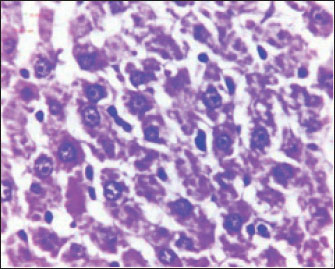

The histopathological results in the TCE group showed that the treatment with TCE for 90 days ( 110 LD50daily) resulted in the infiltration of inflammatory cells, mainly lymphocytes, in portal area with mild fibrosis, hyperplasia of the bile duct (Fig. 3) showed congested central vein, proliferation of Kupffer cells, apoptotic cells and, with dilated sinusoids, while the (Fig. 4) showed severe fatty changes of hepatocytes in the form of cytoplasmic lipid droplets (microvascular steatosis) with proliferation of Kupffer cells. (Fig. 5) showed degenerative changes with necrosis of hepatocytes with proliferation also (Fig. 6). Histopathological section of the liver (group + with oil) showing mild degenerative changes of hepatocytes. In Fig. 7, the histopathological section of the liver (c +group/90 days) showing mild degenerative changes of hepatocytes with few inflammatory cells infiltration (Fig. 8). Finally, in Fig. 9, histological section of the liver (control group) with normal structure.

Fig. 5. Histopathological section of the liver (TCE group/90 days) showing severe fatty changes in hepatocytes in the form of cytoplasmic lipid droplets (microvascular steatosis) with proliferation of Kupffer cells (H&E stain 400X).

Fig. 6. Histopathological section of the liver (TCE group/90 days) showing degenerative changes with necrosis of hepatocytes and proliferation of Kupffer cells ( H&E stain 400X).